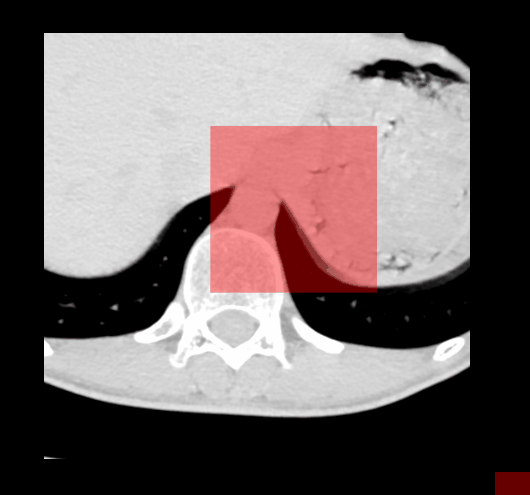

maskFilter->SetMaskedOutputValue(255, 0, 0);

maskFilter->SetMaskAlpha(0.4);

maskFilter->NotMaskOn(); // 255 不可见

4、勾画交互-圆形工具